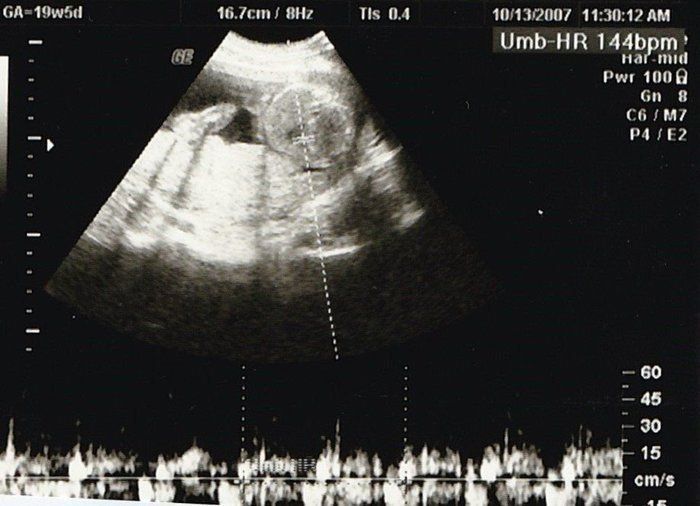

クリコさんの妊娠23週目のエコー写真

推定体重679g。大きくなったためエコー画像に収まらなくなり、胎動もよく感じるようになりました。運動や、母親学級に参加したことで、初めてのママ友ができ、マタニティーライフを満喫。結婚して引っ越してきた土地で、近所に友人もおらず、平日に近所を歩くこともなかったので、毎日がとても新鮮でした。妊娠生活や、地域の情報なども交換でき、有意義な時間がすごせました。ただ、その目的で、お茶やランチをしていたせいか体重はどんどん増えるばかり。